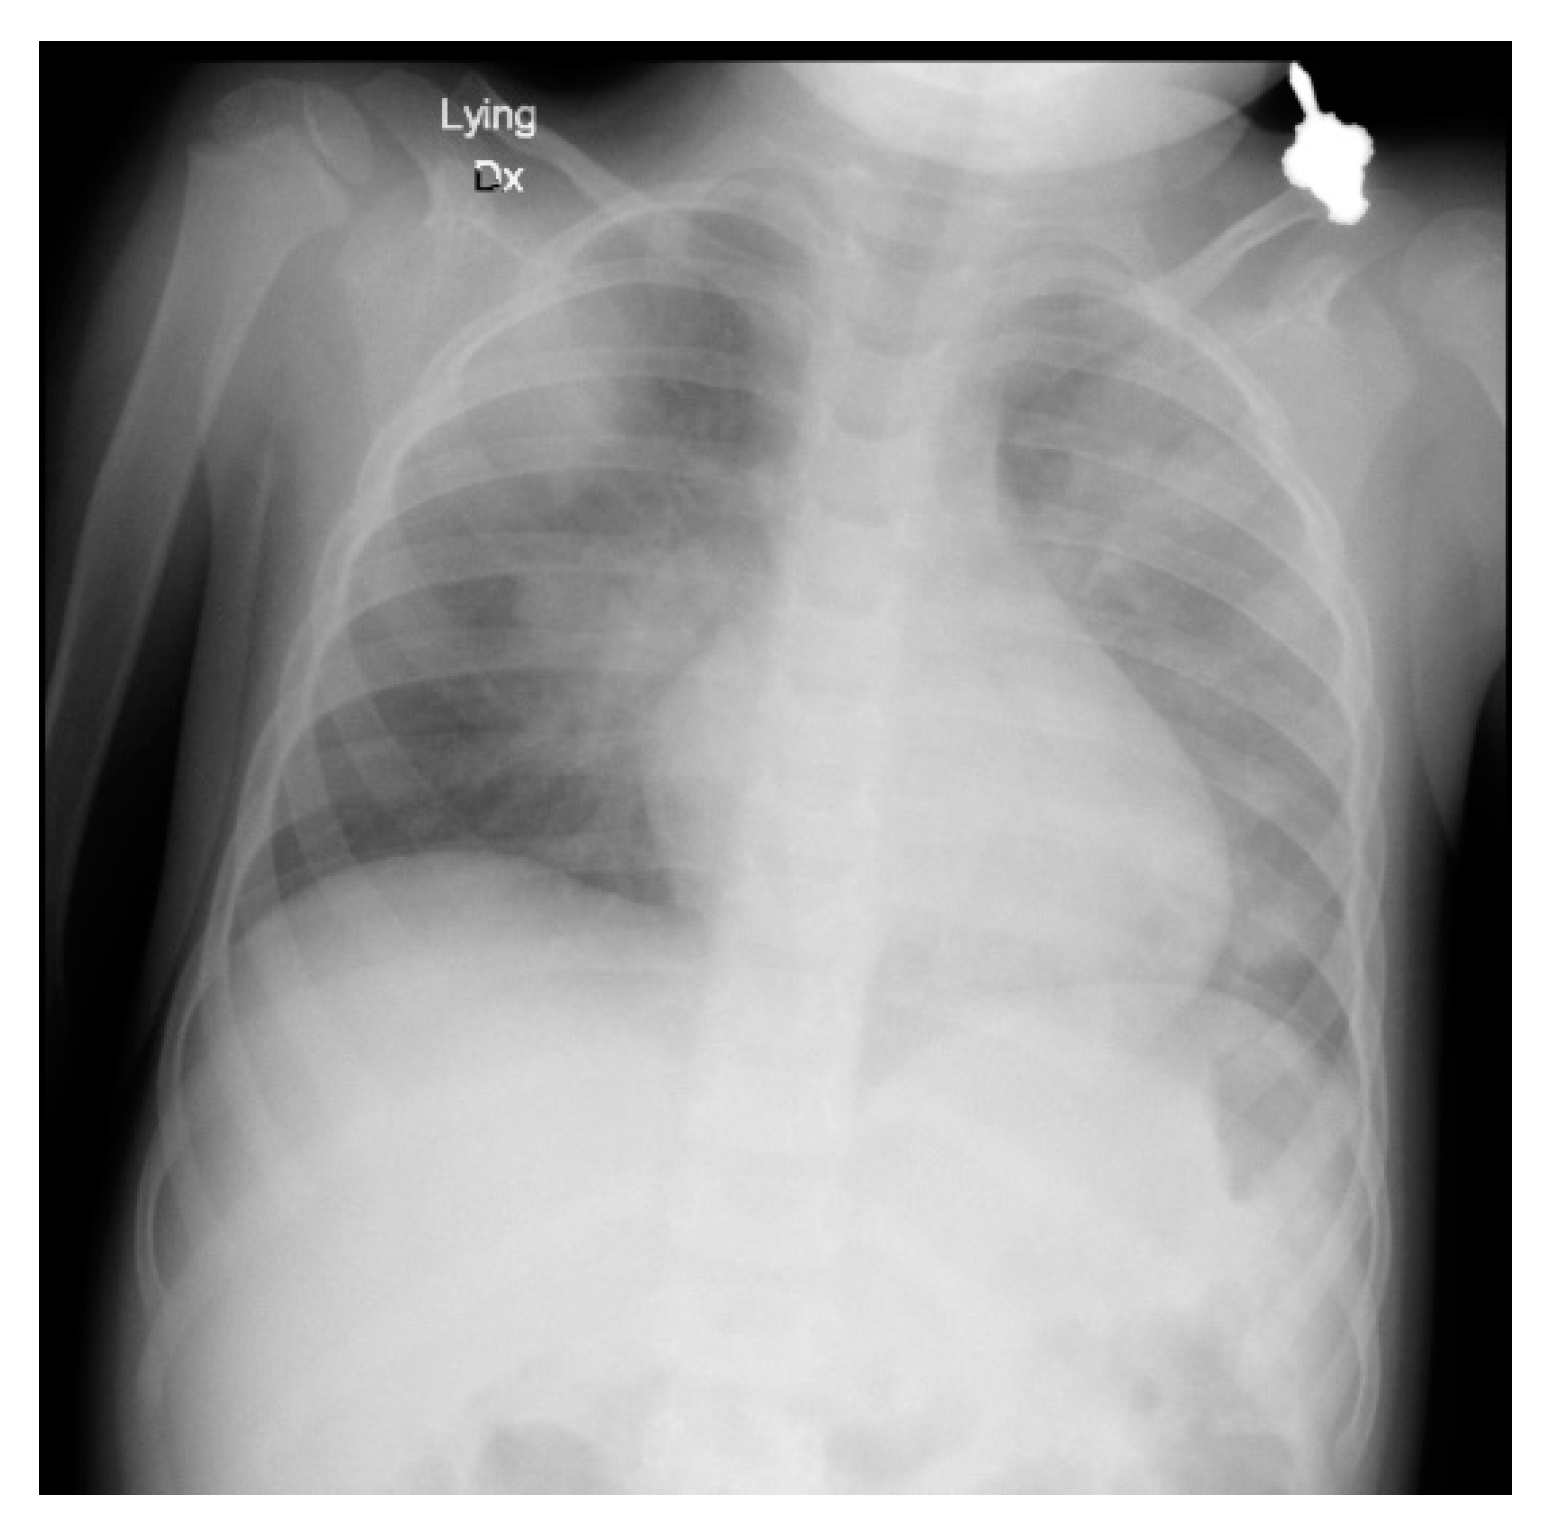

Following the measures taken, the patient’s condition improved with increasing SpO2% levels, resolving respiratory failure on CBG, and gradually clearing signs of pneumonia on the chest X-ray. To prevent respiratory alkalosis, ventilation was switched to CPAP at this point and later on, the patient was extubated.

Following extubation, the patient’s breathing rate was normal at ~16/min. Initially, the patient required oxygen support to maintain SpO2% levels but was gradually weaned off until it was no longer required. A chest X-ray obtained at this stage (Figure 3) demonstrated resolving pneumonia. The patient was then discharged from the PICU and recovered on the ward with normalization of PEWS before discharge (Figure 2). The key interventions provided during the hospitalization period are shown in Table 1.

Figure 3. Day 2 Chest X-ray demonstrating decreased opacification bilaterally indicative of resolving pneumonia.